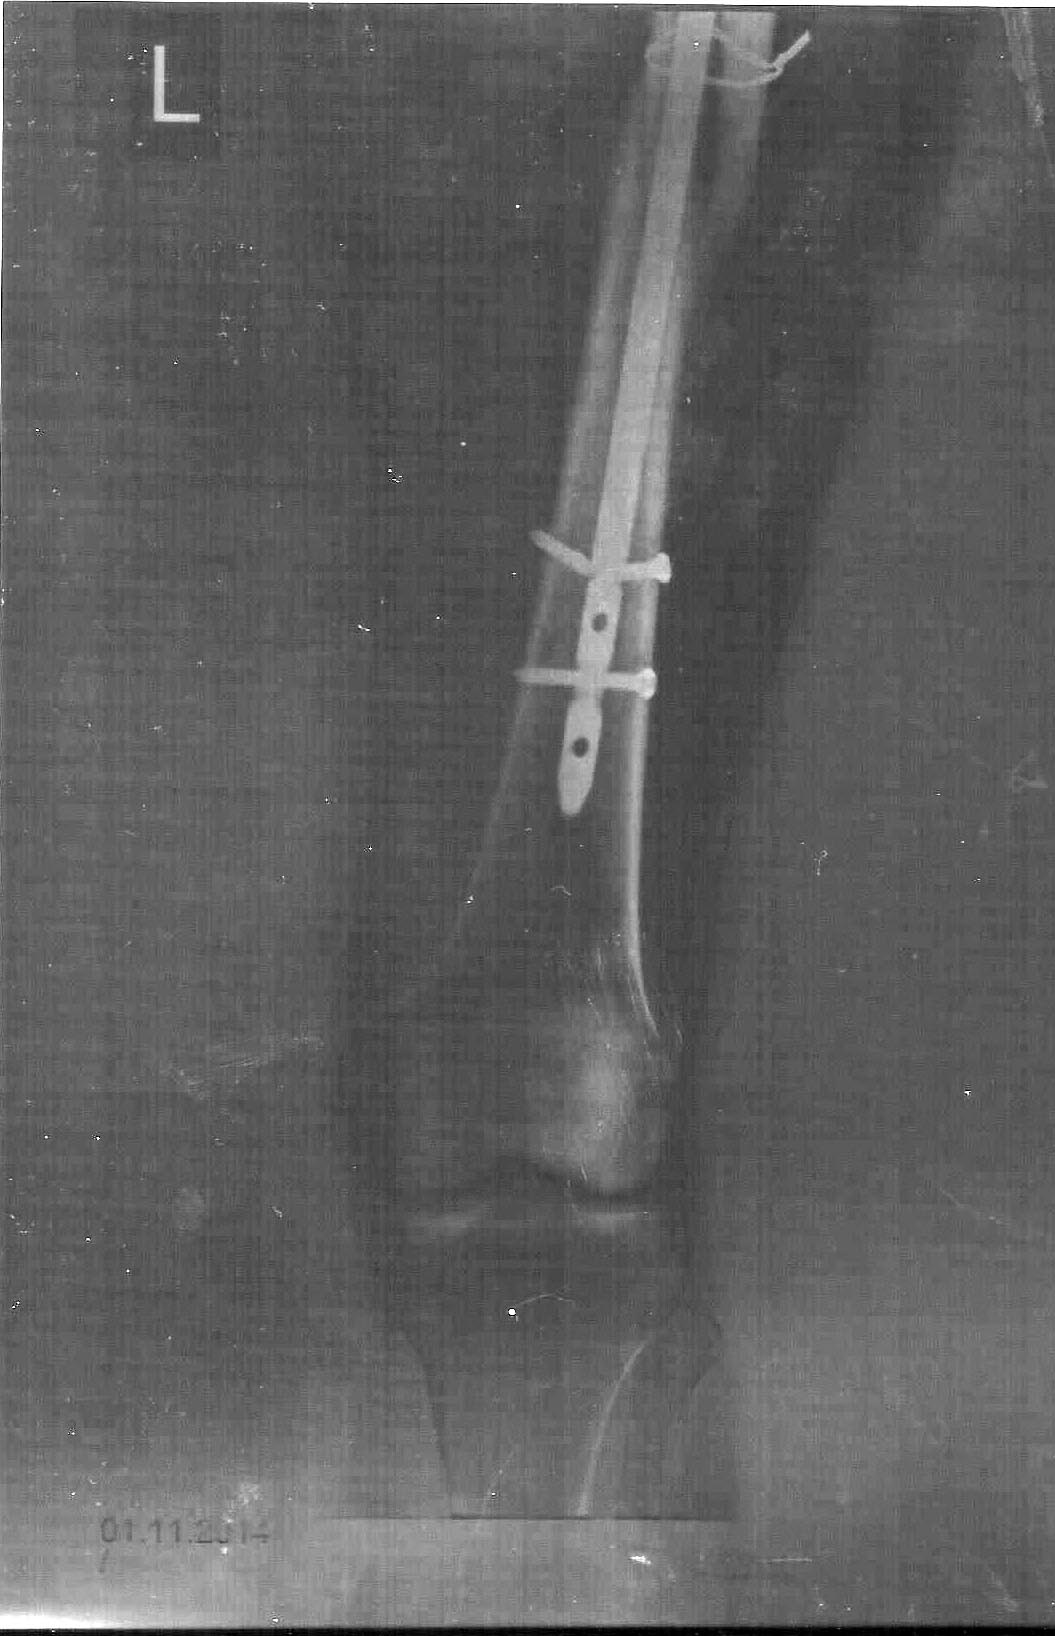

Уважаемые врачи, прошу вас помочь советом в конкретно моем случае. 22 мая 2014 года после дтп была операция по внедрению штифта в мое бедро.

Пару дней назад появилась резкая боль в колене; решил сделать снимок: вот результат сломался саморез внизу штифта! Вопрос - что теперь делать? Опять операция или так оставить? Боль в колене или чуть выше колена терпимая при нагрузке, без нагрузки не болит, ноетСкажите можно ли давать полную нагрузку на ногу? Хожу с одним костылем уже 2 месяца.

И сканировать рентгенограммы офисными сканерами не надо, можно только "просветными", которые мало где есть. Так что нужно их фотографировать напросвет.